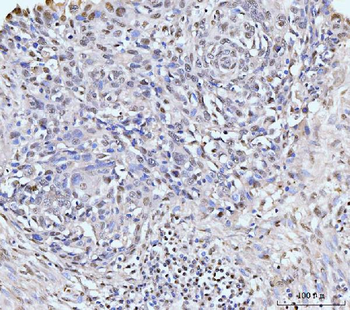

100 μl, 50 μl, 200 μl - HSC70 Mouse Monoclonal Antibody [orb704174]Featured

IF, IHC-Fr, IHC-P, WB

Human, Mouse, Rat

Mouse, Rat

Mouse

Monoclonal

Unconjugated

100 μl, 50 μl, 200 μl - ATF4 Recombinant Rabbit Monoclonal Antibody [orb704304]Featured